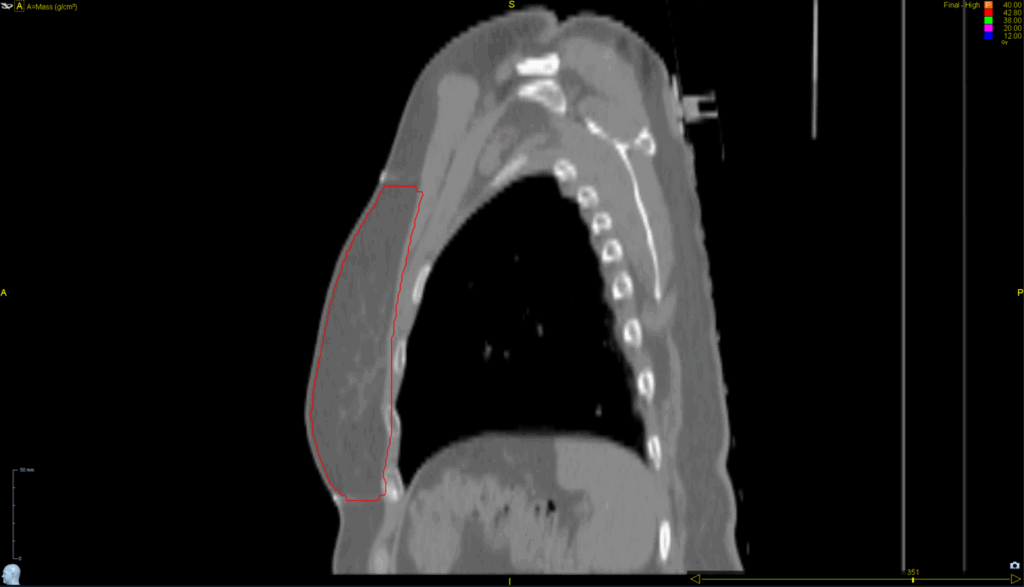

Planning CT Images

PTV(s) Volume, Length

617 cc, 18 cm

- TomoDirect™

- 4 angles

- TomoEDGE™ 5 cm